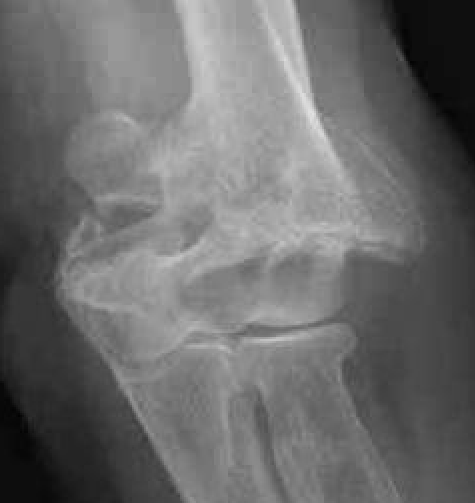

Bag of bones / nonoperative management

Initial injury in elderly patient

Elbow post treatment in cast

Indication

Patient elderly and not operative candidate

Technique

Initial rest in plaster then mobilisation

Results

- 40 "elderly and low demand" patients treated non-op

- 5 year mortality 40%

- 50% non union

- DASH score 38/100

- modest function, but avoids risks